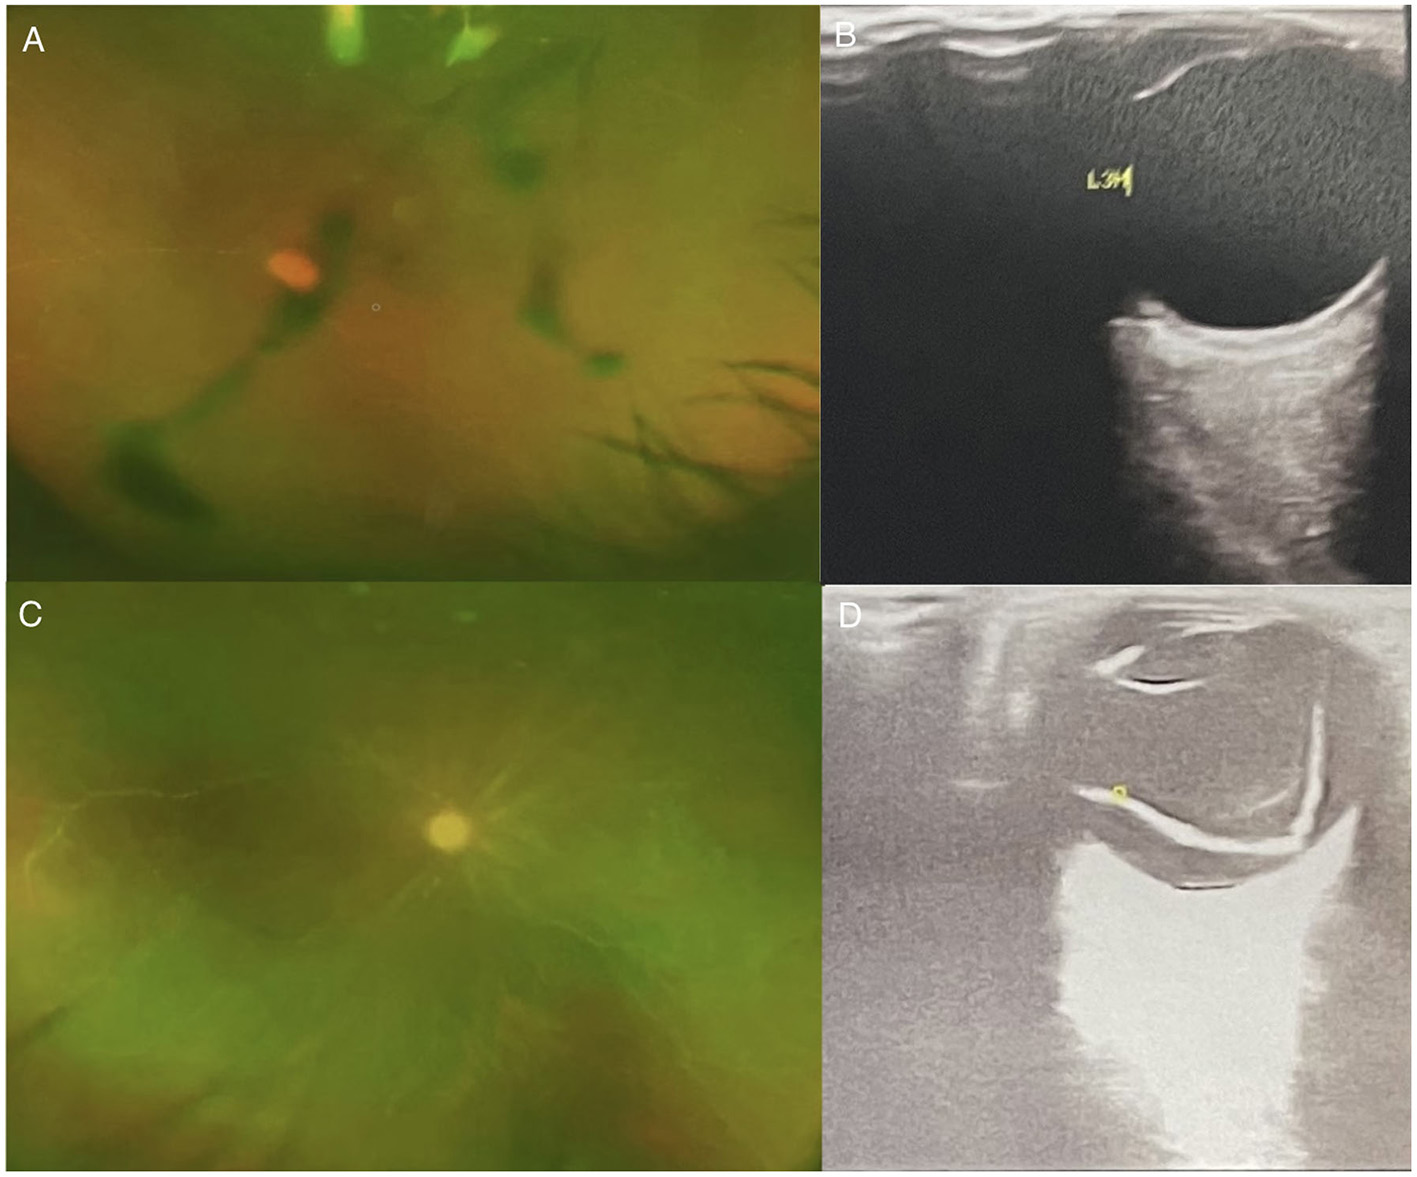

Figure 2. (A) Ophthalmology wide-angle lens examination-L; (B) Ophthalmic Ultrasound-left: The left eye ring is intact, the lens wave is visible, and the dark area of the vitreous body is moderately diffuse. Spot flocculent weak echo and mass echo, and the posterior wall of the ball is slightly thickened. There is no obvious thickening of the four rectus muscles. (C) Ophthalmology wide-angle lens examination-R; (D) Ophthalmic Ultrasound-right: The right eye ring is intact, the lens wave is visible, and low and medium amount of diffuse spot flocculent weak echo and cluster echo are seen in the dark area of the vitreous body. Both the horizontal axis and the vertical axis can be detected in the vitreous “shaped echo” band echo. The tip is connected with the optic papilla, and the two ends are connected with the peripheral spherical wall.